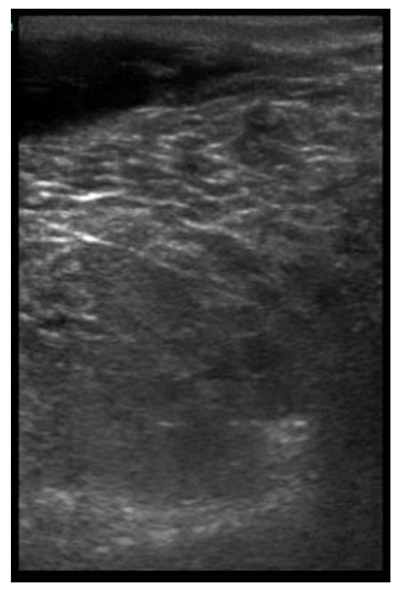

The image processing was undertaken using ImageJ software [28] as used by Abràmoff et al. [29]. The scales between pixels and millimetres were calculated based on the number of pixels, the scanning depth (mm), and the transducer width (mm) (Figure 4). This method relies on the ability of the operator to interpret and identify lines on the images. To standardize the assessment compartment depth, drawing templates were created for each time point as used by Molenaar et al. [30] and included four representative images from four different yearling ewes with and without the lines drawn for each compartment (Appendix A). The total depth of mammary gland conservative (MTc) was the smallest likely demarcation (abdominal wall) of the mammary gland (Figure 5a), and total depth of the mammary gland generous (MTg) was the largest likely demarcation of the mammary gland visible on the image [30] (Figure 5a). The MTc, MTg, fat pad (FP), parenchyma (PAR), and gland cistern (GC) depths were estimated at the deepest point for each sub-compartment, excluding the skin layers, using the straight tracer (Figure 5a) and were expressed in millimetres.

Figure 5.

(a) Demonstration of delimitations of the mammary total depth conservative (MTc) and generous (MTg), mammary gland cistern (GC), parenchyma (PAR) and the fat pad (FP) and (b) Demonstration of randomly positioning of regions of interest (1, 2, 3) in the parenchyma.

Appendix A. Drawing Templates of Mammary Ultrasound Images in Late Pregnancy, Early Lactation and Weaning in Yearling Ewes

Drawing template of mammary ultrasound images in early lactation (29 days of lactation; L29) in four different yearling ewes.